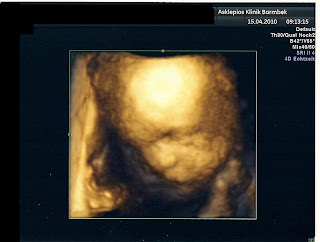

Da wir so früh dort waren hat Kyra noch geschlafen *Grins* dadurch konnten wir uns Die rechte Gesicht hälfte anschauen, die Lippen-Kiefer-Gaumen Spalte ist auf jeden Fall größer als 5 Millimeter bei dem Ultraschall haben wir gesehen das die spalte von der Rechte Seite bis zur Mitte des Gesichtes

geht.

So hier habe ich noch ein Paar Bilder.